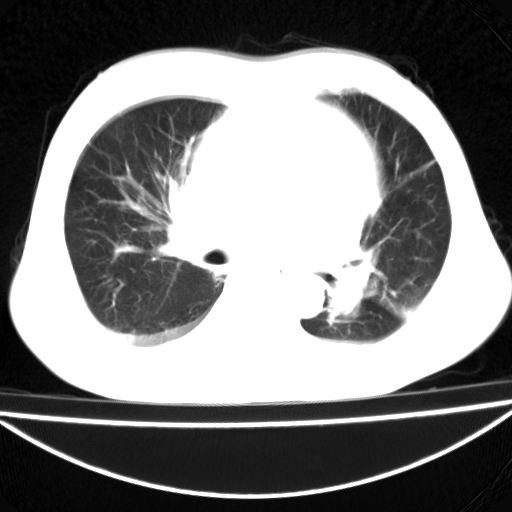

以下是引用zhangzhongshou在2008-6-23 12:26:00的发言:[br]结合临床,考虑心衰并肺水肿 ,双侧少量胸腔积液。心脏病性质待定,建议进一步检查。

以下是引用zhangzhongshou在2008-6-23 12:26:00的发言:[br]结合临床,考虑心衰并肺水肿 ,双侧少量胸腔积液。腹水。心脏病性质待定,建议进一步检查。